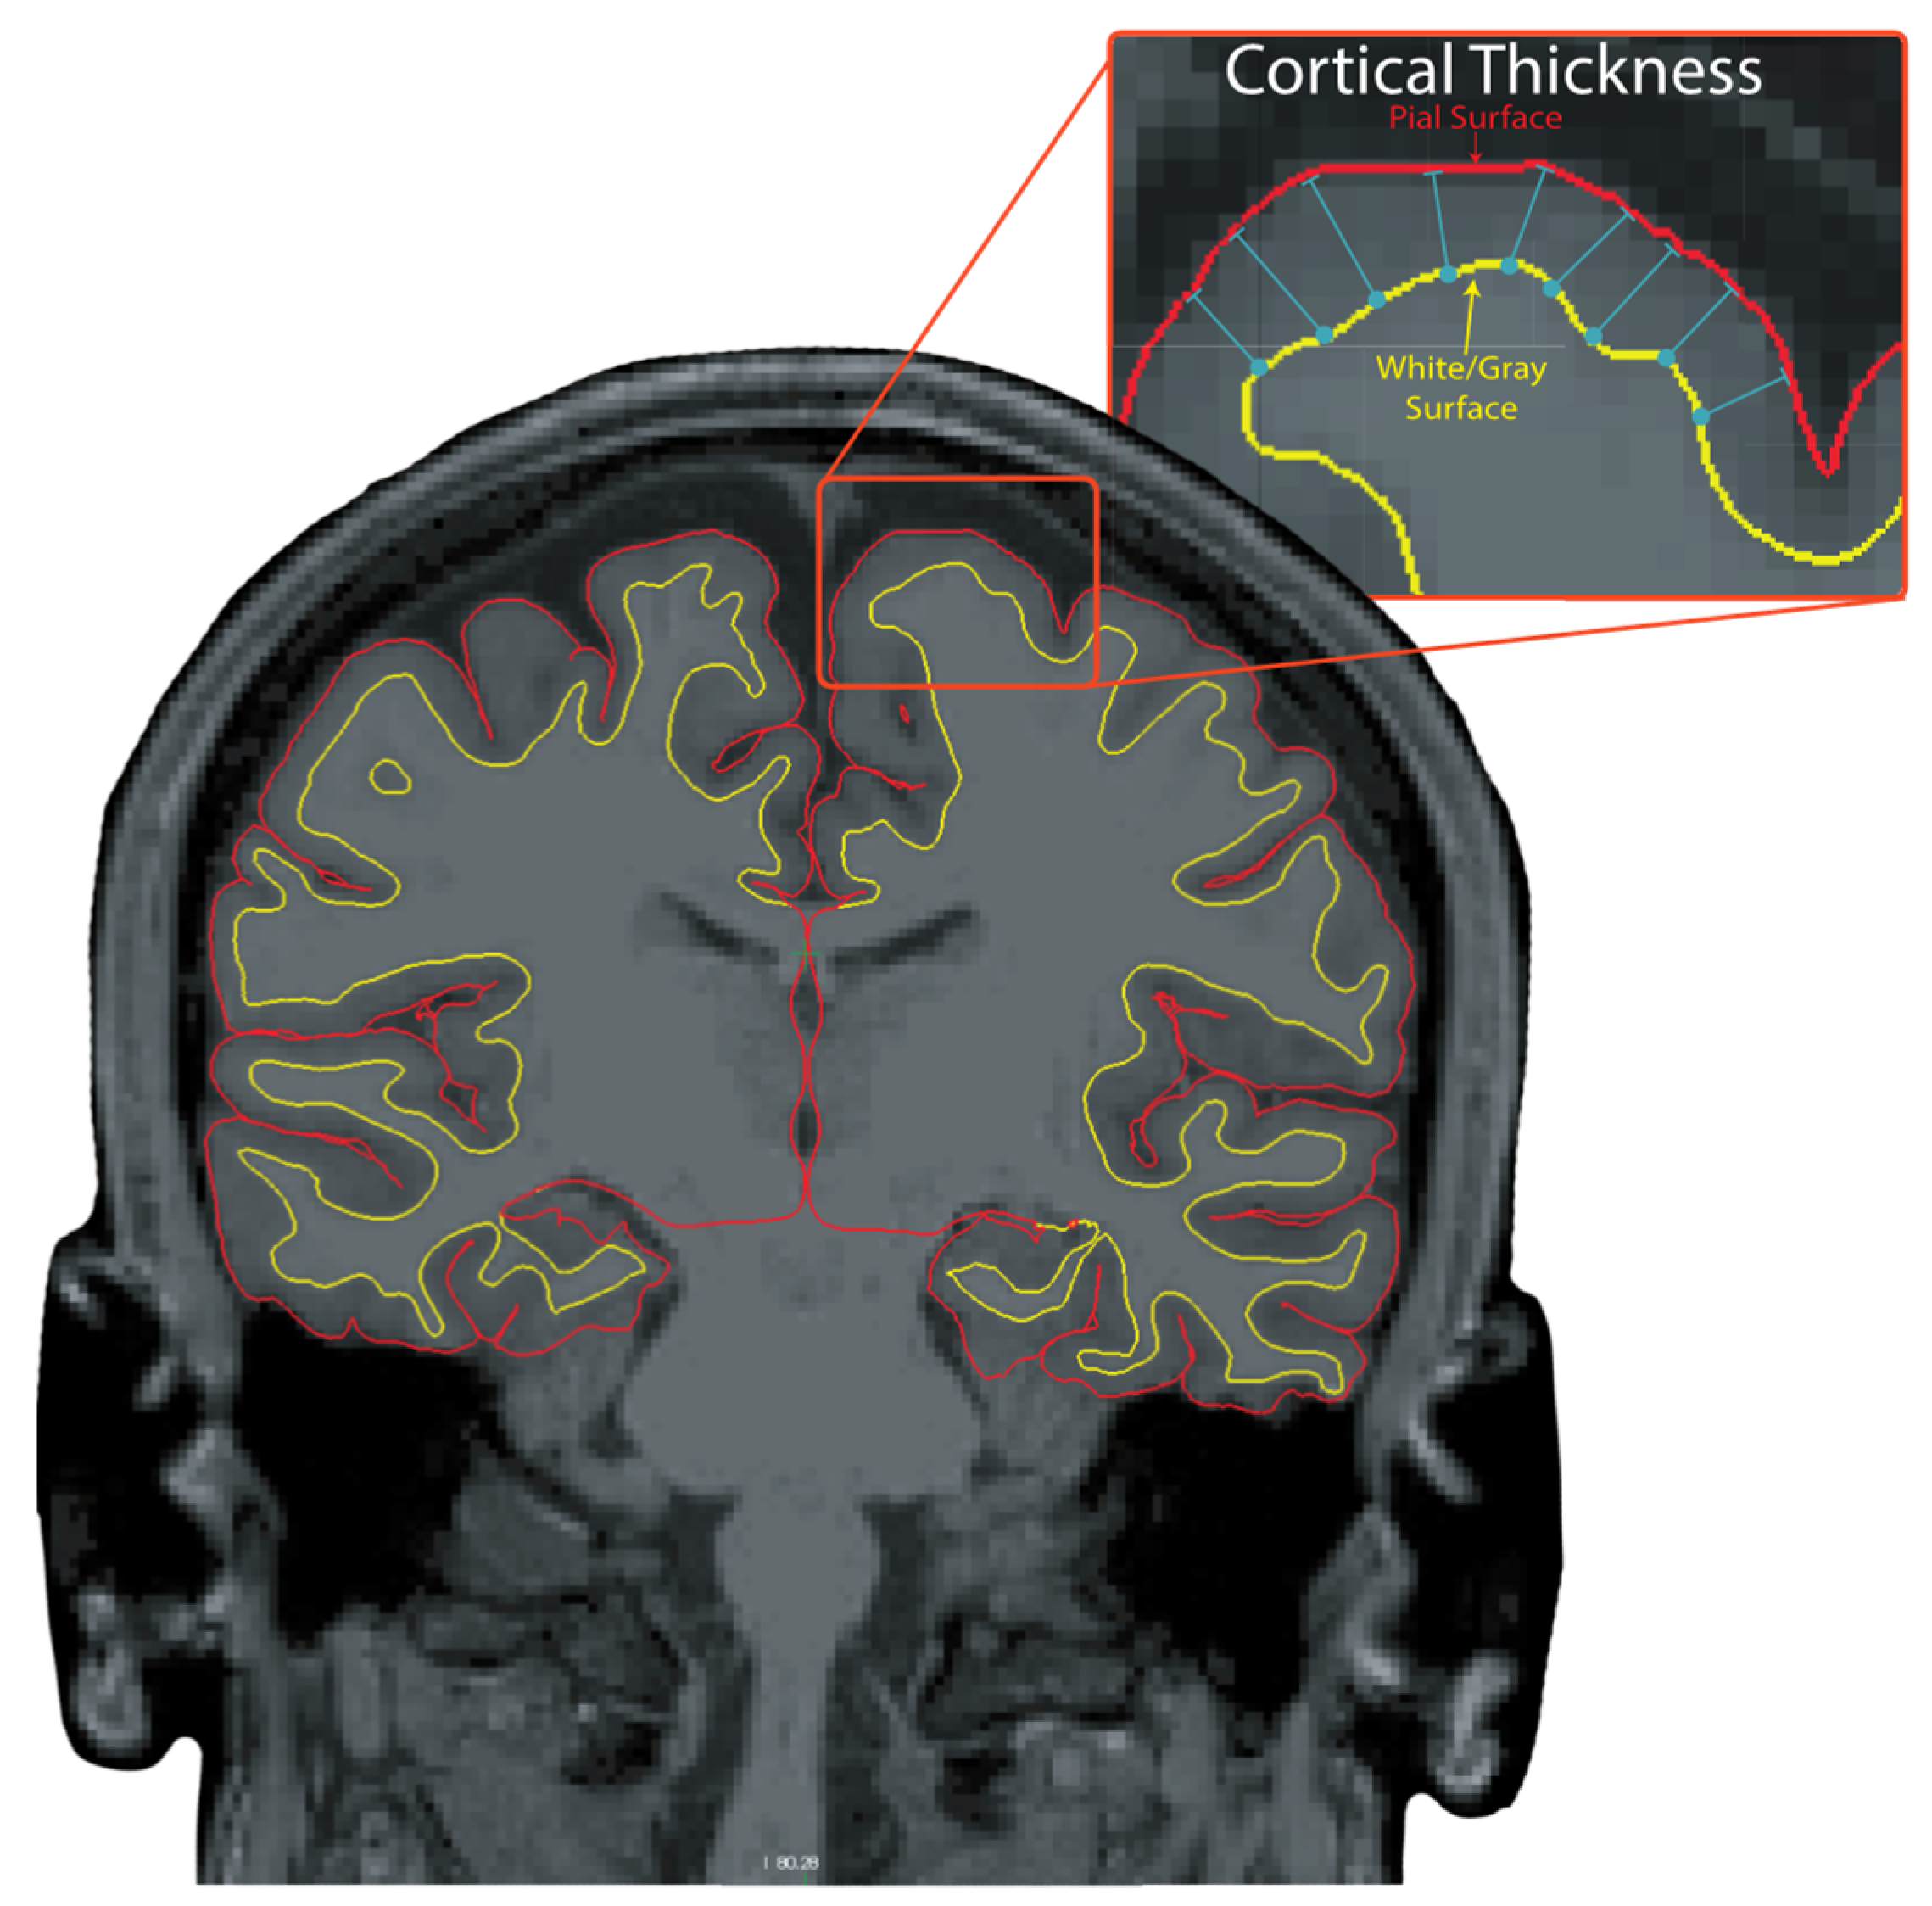

- Fischl, B.; Dale, A.M. Measuring the thickness of the human cerebral cortex from magnetic resonance images. Proc. Natl. Acad. Sci. USA 2000, 97, 11050–11055. [Google Scholar] [CrossRef]

- Lindroth, H.; Nair, V.A.; Stanfield, C.; Casey, C.; Mohanty, R.; Wayer, D.; Rowley, P.; Brown, R.; Prabhakaran, V.; Sanders, R.D. Examining the identification of age-related atrophy between T1 and T1 + T2-FLAIR cortical thickness measurements. Sci. Rep. 2019, 9, 11288. [Google Scholar] [CrossRef]